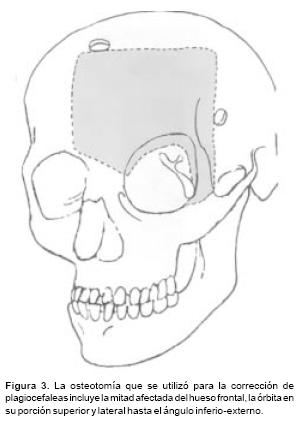

Las osteotomías a utilizar se diseñan previamente en las reconstrucciones tridimensionales obtenidas con la T.A.C., y ésta varía de acuerdo a la deformidad de cada paciente. Las más utilizadas son: osteotomías fronto–orbitarias bilaterales (Figura 1), osteotomía tipo monobloque (Figura 2) y osteotomía fronto–orbito–malar unilateral (Figura 3). La osteotomía seleccionada se dibuja sobre la estructura esquelética disecada utilizando violeta de genciana. En este momento se selecciona 2 o 3 sitios sobre el hueso frontal para las craneotomías. Y una vez completadas estás, se realiza una disección intracraneana muy limitada que sigue las líneas de las osteotomías en el área frontal y orbitaria, creando una serie de túneles intracraneanos y preservando la mayoría de los puentes vasculares entre las meninges y el hueso frontal. El mismo procedimiento se utiliza para el techo orbitario. A través de los túneles se introducen tiras de gasas y separadores muy finos que permiten la realización de las osteotomías con sierras oscilatorias, sin daño a las estructuras subyacentes. Con un endoscopio rígido de visión directa se verifica la hemostasia y la integridad de las meninges luego de realizar las osteotomías. Así mismo bajo visión endoscópica se realiza una cuidadosa disección del área de la Crista Galli y de las alas menores del esfenoides en su unión con la órbita y el frontal, lo que permite completar las osteotomías a nivel central y lateral y la movilización de toda la estructura ósea a avanzar. En los casos de monobloque, la línea de osteotomía se continúa de la pared lateral orbitaria a la unión pterigomaxilar y sobre el piso y la pared medial de la órbita. En estos casos la disyunción con pinzas de Rowe del área pterigomaxilar, se hace necesario a fin de avanzar en un verdadero monobloque el maxilar unido a las órbitas y al hueso frontal (Figura 2).

En las plagiocefalias realizamos una osteotomía que avanza sólo la mitad deformada (Figura 3). Ésta es una osteotomía que se adapta a la gravedad de la deformidad en la órbita y en el malar. Cuando el malar está hipoplásico la osteotomía se extiende hasta incluirlo. En todos los casos la osteotomía se extiende entre 15 y 20 mm., pasando la línea media frontal, luego baja, atraviesa el nasión y llega al ángulo supero–interno de la órbita, incluyendo el techo y continuándose por el mismo hasta llegar al lado contralateral. En estos casos el avance se realiza a manera de bisagra, debido a que en la porción medial de la frente se efectúa osteotomía en rama verde, mientras que en la porción lateral y de la órbita se efectúa una osteotomía total. Los distractores se apoyan con un vector semioblicuo (a 25° sobre el plano de Francfort), en la unión fronto– orbitaria, avanzando más importantemente la porción lateral, mientras que la osteotomía en rama verde funciona como un pivote medial.